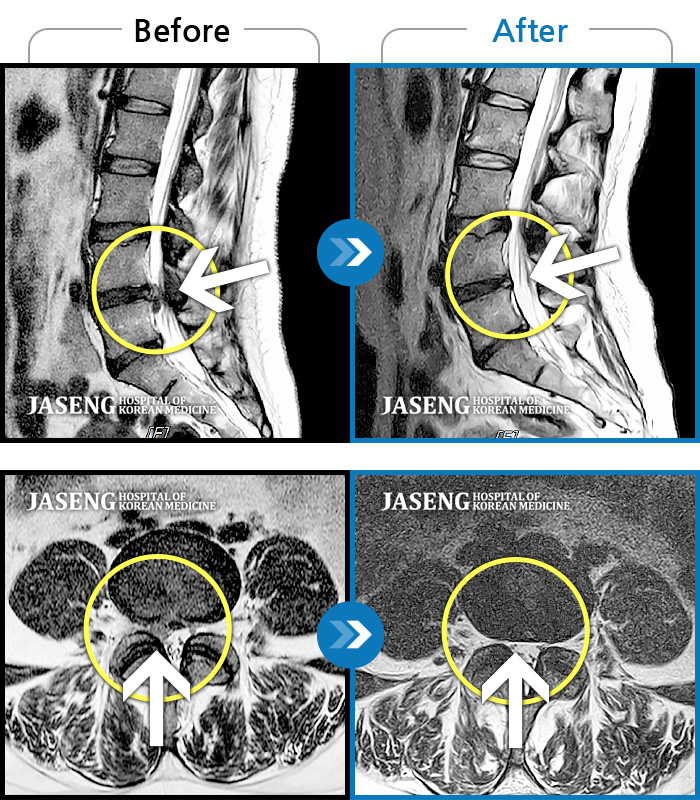

너무나도 아파서 즐겨하는 볼링도 더 이상 할 수 없고 남은 내 삶도 끝장이라는 생각이 들어서 반신반의하며 찾은 자생한방병원. 일반병원에서 무조건 수술하라고 한 상태였지만 허리는 수술하면 아좋다는 이야기를 많이 들었던 터라 상담이나 받아보고 결정해야겟다는 마음으로 들렀는데 첫날 강만호 원장님께서 저의 MR 사진을 분석하시면서I 수술하지 마시고 저를 믿고 치료하면 반드시 낫는다고 자신있게 말씀을 해주셨습니다. 너무나 친절한 말투와 환자 입장에서 진솔하고 성의있는 태도로 환자가 아ㅣㄹ고싶어 하는 치료과정과 환자의 심리적 요인까지 배려하시는 모습에서 믿음이 들어 지금까지 치료를 받고 있습니다. 지금은 걷지도 못하던 제가 일상생활에 아무런 지장이 없고 즐겨하던 볼링도 칠 수 있게 된 것이 굼만 같습니다. 지금 간혹 통원치료를 다니고 잇는데 원장님 이하 담당 간호사님 그리고 병원 구성원 모두가 너무나도 친절하고 밝은 모습으로 따뜻하게 맞이해주셔서 마치 내집같은 생각이 들곤 합니다..